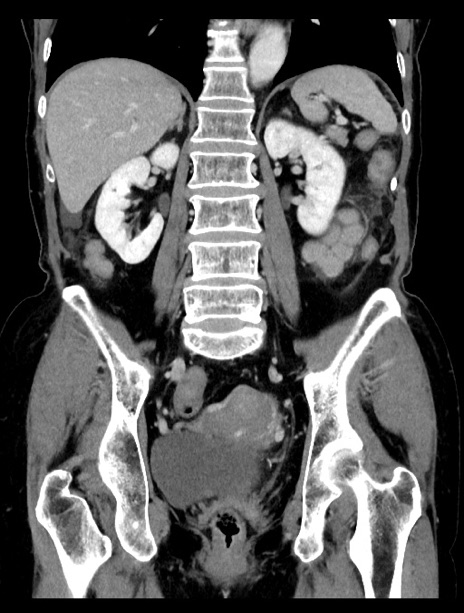

症例23(冠状断像)

【症例】70歳代女性

【主訴】下腹部痛・嘔吐

【現病歴】2日前より腹痛あり。昨日嘔吐あり。症状改善しないため来院。

【既往歴】胃GISTに対して胃部分切除後。

【身体所見】BT 37.1℃、BP 128/77mmHg、腹部:平坦・軟、下腹部に圧痛あり。

【データ】WBC 10200、CRP 0.31